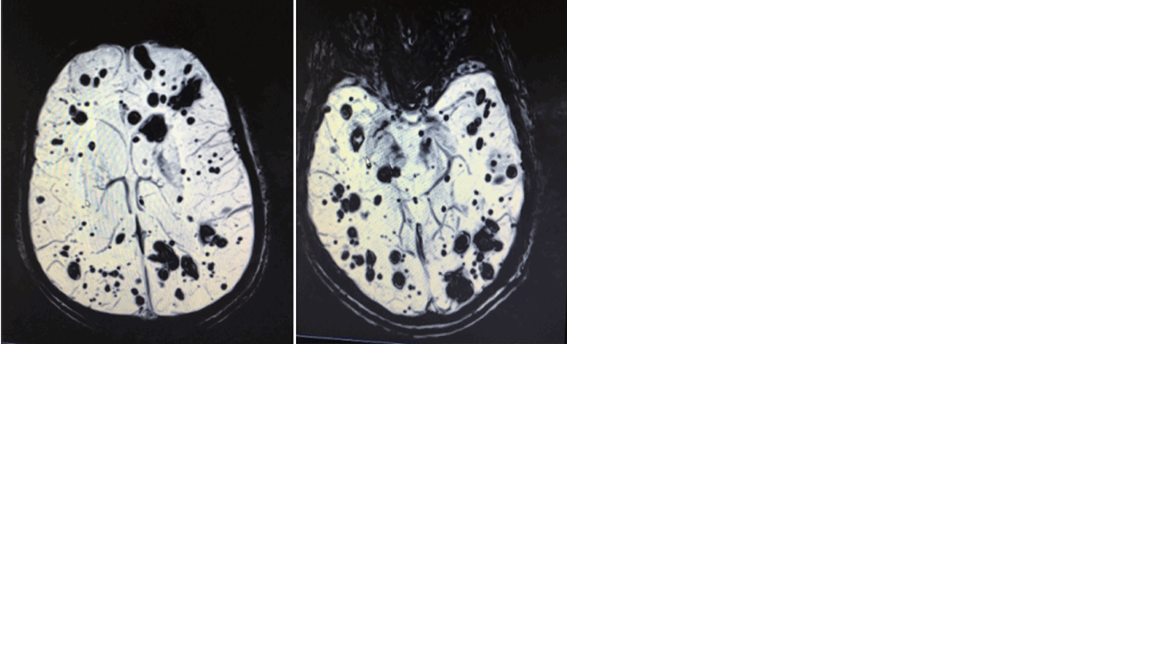

Se ingresa al paciente a cargo de Neurología para completar estudio y en vista del mal estado general del paciente, que no tolera la ingesta oral por los vómitos. En la RM cerebral se muestran múltiples lesiones hemorrágicas de distintos tamaños y en distintos estadios supra e infratentoriales bilaterales, sugestivas de cavernomatosis múltiple. Se observan dos focos de sangrado agudo, precentral derecho y hemibulbar izquierdo, esta última con extenso edema adyacente. El estudio del polígono de Willis sin alteraciones. Se solicita estudio genético, que queda pendiente al alta del paciente.

La cavernomatosis es una malformación vascular del sistema vascular cerebral, a menudo con componente genético. Las principales manisfestaciones clínicas son las hemorragias intracerebrales, las crisis epilépticas y las cefaleas, y dependen de la localización, del tamaño, y del número de cavernomas. El disgnostico se realiza mediante TAC y RM, viéndose en la primera a menudo imágenes localizadas de densidad elevada en relación con las hemorragias (asociado algunas veces a calcificaciones) que según el estadio del sangrado presentaran efecto masa y o edema. Con la resonancia cerebral se identifican lesiones caracetristicamente “en palomitas de maíz”, que son zonas redondeadas hipointensas, circunscritas por un halo hiperintenso de hemosiderina. Los estudios angiográficos, por su parte, son de poca utilidad para el diagnostico de la cavernomatosis, pero si que tiene alta sensibilidad para las malformaciones vasculares asociadas. El tratamiento dependerá del número, la localización y las complicaciones derivadas del sangrado. En el caso de este paciente, uno de los diagnósticos que nos planteábamos ante los resultados del TAC, que informaban de posibles hemorragias, era en relación con el consumo de cocaína y la vasoconstricción que esta produce. Sin embargo, tras los resultados de la RMN, vemos que ya había una patología genética previa, desconocida hasta este momento. Aun así, no podemos descartar que los dos focos de sangrado no tengan cierta relación con el consumo de drogas.